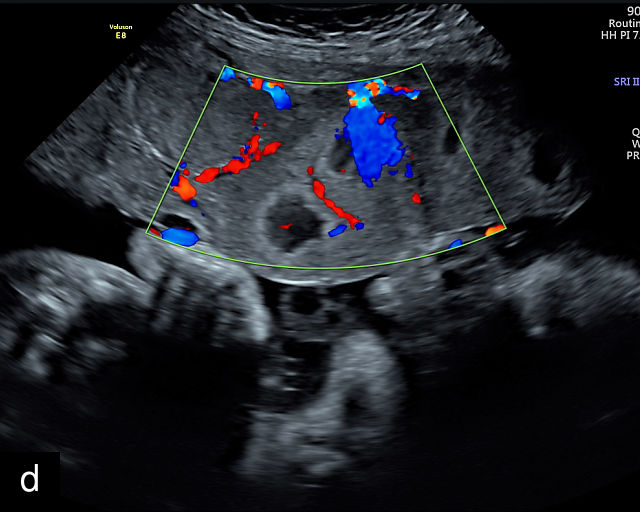

6

Placenta accreta spectrum. (a,b) Sagittal transabdominal grayscale ultrasound of the lower uterus and cervix demonstrating placenta previa accreta, with the placenta (p) containing prominent irregular hypoechoic lacunae. There is absence of the myometrium at the bladder (b) interface (arrows) c, cervix. (c) Sagittal transabdominal color Doppler ultrasound of the lower uterus and cervix demonstrating placenta previa accreta, with increased vascularity of the lower uterus and the myometrial bladder interface. (d) Transvaginal ultrasound of placenta previa accreta showing multiple lacunae involving the cervix with no clear demarcation between the placenta and the cervix. (e) Transvaginal ultrasound of placenta previa accreta showing multiple large irregular lacunae involving the cervix with no clear demarcation between the placenta (p) and the cervix. The placenta has a ‘moth-eaten’ appearance. There is loss of myometrium (arrows). (f) Transvaginal ultrasound of placenta previa accreta without and with color flow Doppler showing multiple large irregular lacunae. The placenta has a ‘moth-eaten’ appearance. There is hypervascularity of the myometrial interface. (g) Transvaginal ultrasound of placenta previa accreta showing multiple lacunae involving the cervix with no clear demarcation between the placenta and the cervix. (h) Transvaginal ultrasound of placenta previa accreta with color flow Doppler showing hypervascularity of the myometrial interface and irregularity of the bladder wall. b, bladder; p, placenta. (i) Transabdominal grayscale ultrasound of cesarean scar pregnancy. The uterine fundus (f) is empty (arrowhead). The gestational sac (arrow) is located in the lower uterus, anterior to the uterine canal, and lies above the cervix (c). b, bladder. (j) Transvaginal grayscale ultrasound image of cesarean scar pregnancy showing the empty fundus (f) and the normal cervix (c). The gestational sac lies below the fundus, above the cervix and anterior to the uterine cavity. (k) Transvaginal grayscale ultrasound image of cesarean scar pregnancy showing the empty cavity (arrowheads) of the uterine fundus (f), and the normal cervix (c). The gestational sac lies below the fundus, above the cervix and anterior to the uterine cavity (arrow).

Several characteristic sonographic findings are associated with PAS.90,95,96,97 These include placental lacunae, which appear as hypoechoic, irregular spaces within the placenta with high-velocity turbulent flow on color Doppler.16,50 Other features include obliteration of the retroplacental clear space, thinning of the myometrium in the lower uterine segment, irregularity and hypervascularity of the myometrial–bladder interface, and placental bulging into the bladder (Figure 6a–h).90,96,98,99